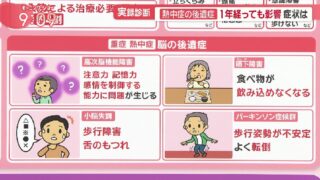

嫌儲「熱中症でぶっ壊れた脳は二度と元に戻らない」らしい。ヤベエよ、とうとう日傘を買う時が来たわ。